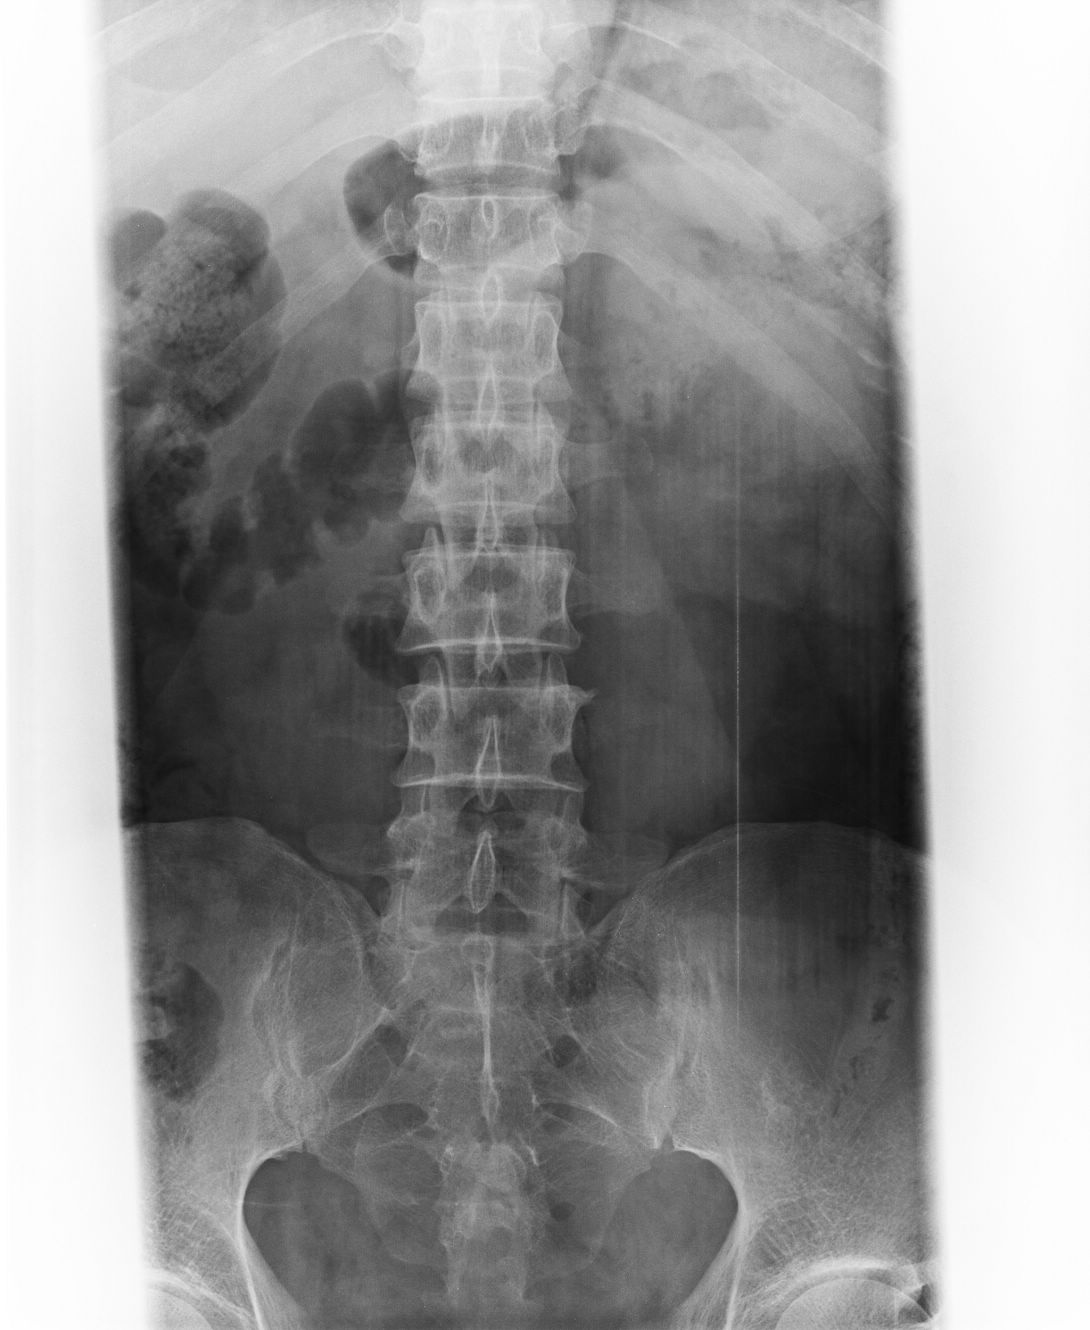

以下是引用liaoqiang在2008-9-2 15:27:00的发言:[br]耻骨联合分离。当心有尿道、膀胱损伤可能。

以下是引用杀毒软件在2008-9-2 17:20:00的发言:[br]支持 -------耻骨联合分离,骶骨近左侧耳状面骨折.

以下是引用随光逐影在2008-9-2 16:56:00的发言:[br]支持 耻骨联合分离,骶骨近左侧耳状面骨折并左侧骶髂关节分离。

以下是引用dyqct在2008-9-2 15:42:00的发言:[br]耻骨联合分离,左侧骶髂关节半脱位。建议ct进一步检查。